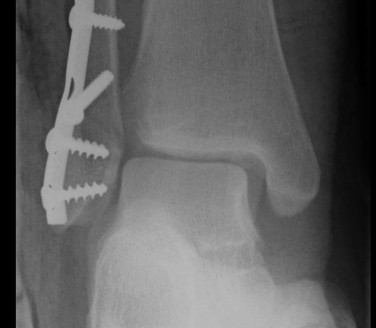

External fixation

Unstable reduction / swelling / poor skin / blisters

Ankle ex fixANkle ex fix